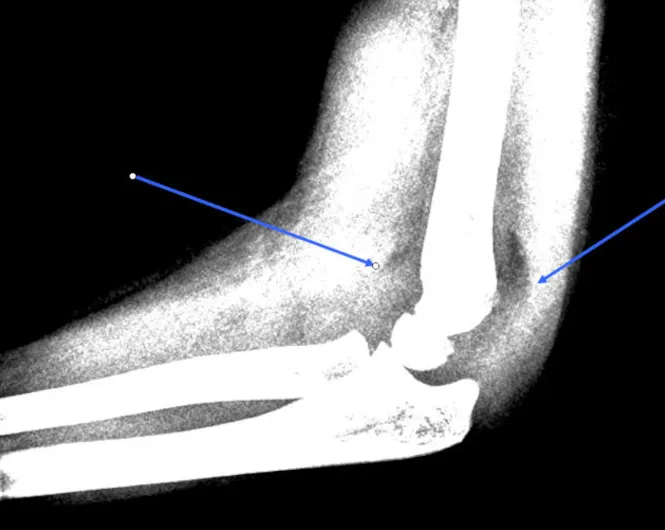

Humerus fraktur

Skadekonf: Der ses udisloceret fraktur af tub majus ve prox humerus samt udisloceret avulsionsfraktur af spids af laterale malleol hø.